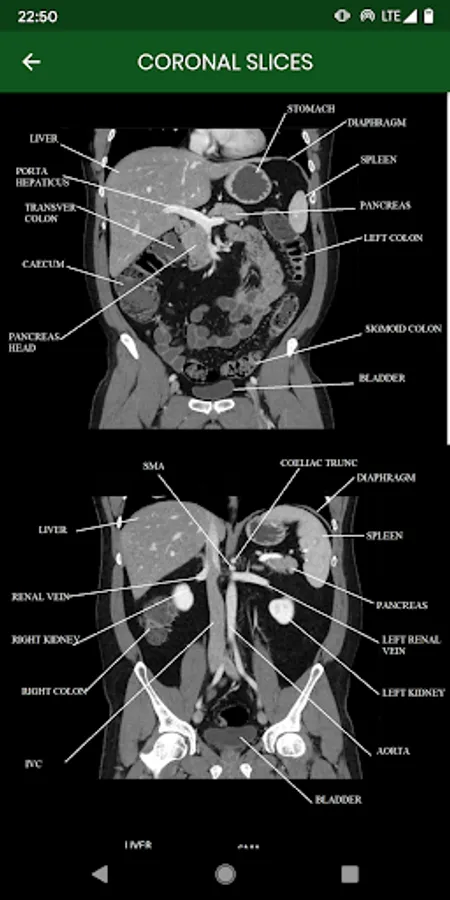

abdominal CT: annotated slices

this app is made for educational purpose. it will help beginners to recognize the normal anatomy of the abdomen examined in CT

abdominal CT: annotated slices Screenshots